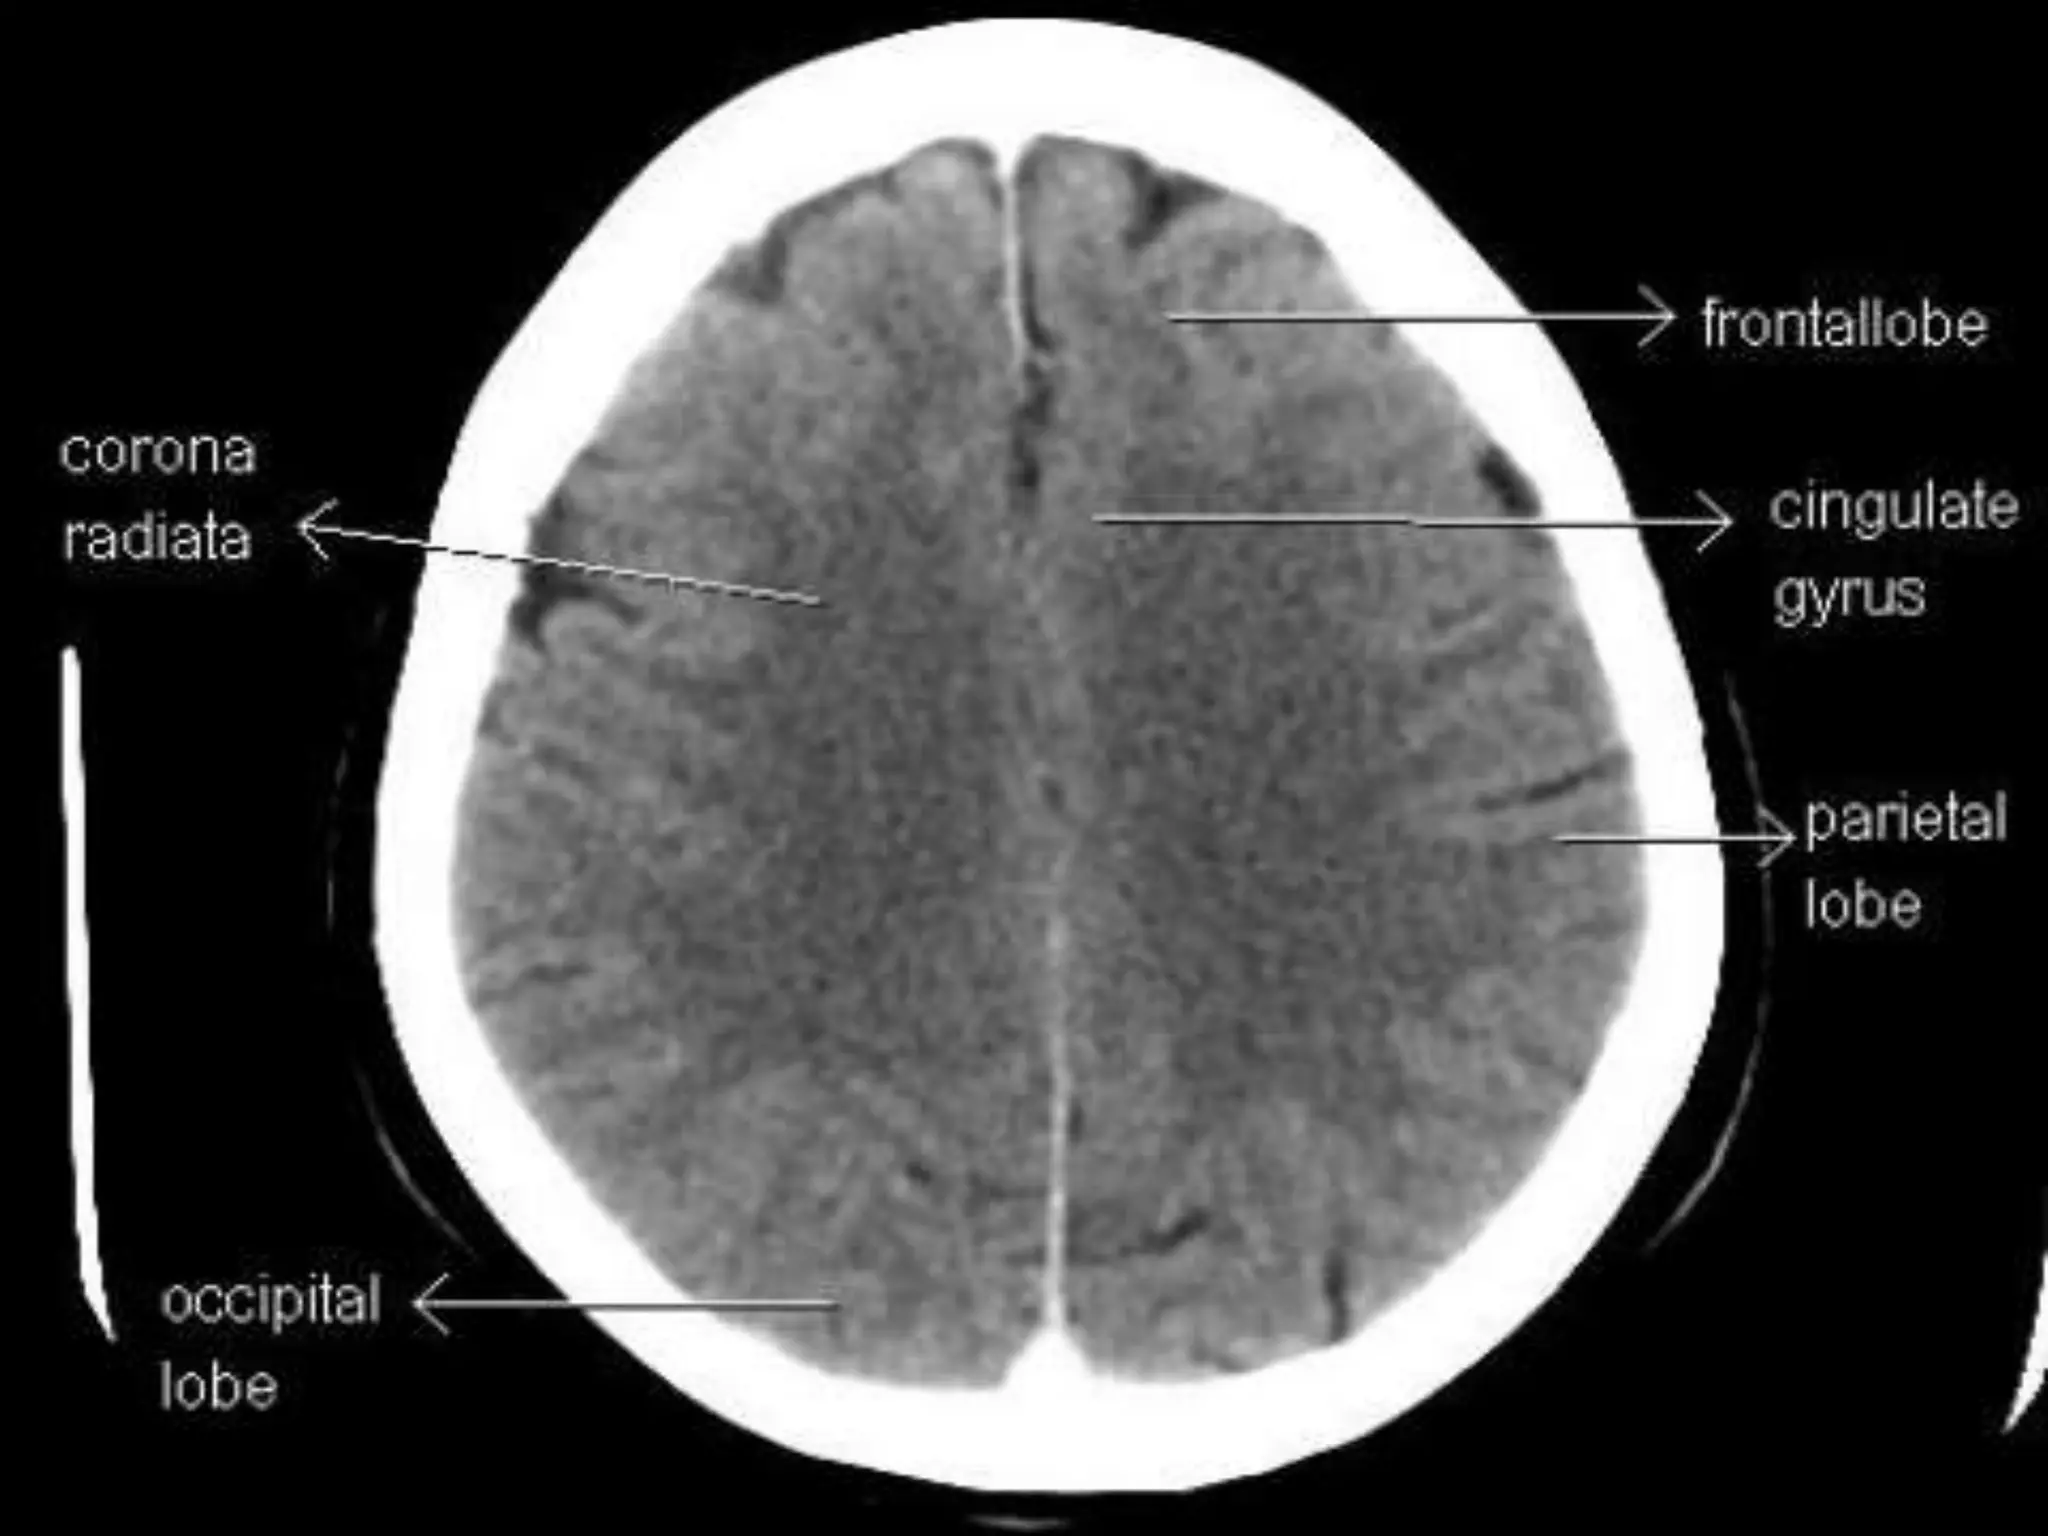

Sectional Anatomy: NormalAxial CT and MRI Anatomy. On CT and MR scans, the brain has been briefly viewed in infratentorial and supratentorial sections, as described below. CT scans are performed with a 15- to 20-degree angulation to the canthomeatal line at 8-mm increments. MRI scans are generally obtained parallel to the AC-PC line in the axial plane with 6-mm slice thickness. Using the sagittal view, the coronal sections are acquired parallel to the brain stem, and the sagittal sections are obtained perpendicular to the axial section. On MRI studies, cranial nerves IX and X can be demonstrated at this level because they emerge from the postolivary sulcus. The posterior aspect of the cerebellar hemispheres is outlined by the inferior portion of the cisterna magna.